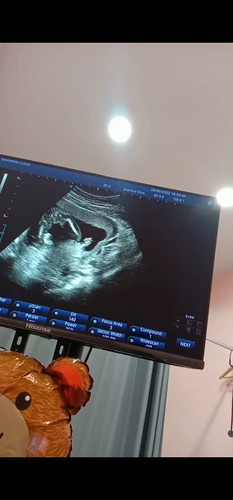

เราท้องแรก แม่ๆว่า น้อง ช หรือ ญ คะ ในภาพนี้ คุณหมอยังไม่คอนเฟิร์มแต่คุณหมอบอกน้องน่าจะเป็น ผู้หญิง 17w3d